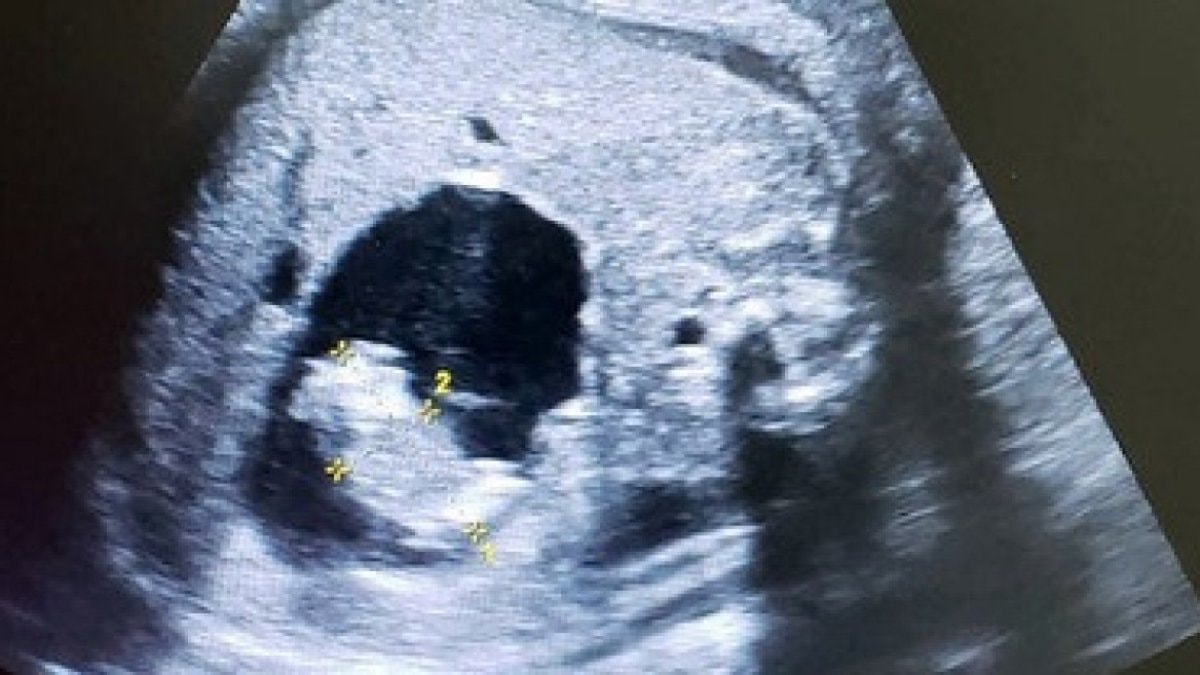

Doktorlar, doğmamış bebeğin ultrasonunda ilginç bir görüntüyle karşılaştı.

Ultrasonda, dünyaya gelmemiş bebeğin karnında, iki fetüs daha bulunduğu gözlemlendi.

Başlangıçta normal seyreden hamilelikte önceki taramalarda herhangi bir sorun görülmedi. Ancak son kontrolde fetüsün karnında kemik içeren anormal bir yapı fark edildi.